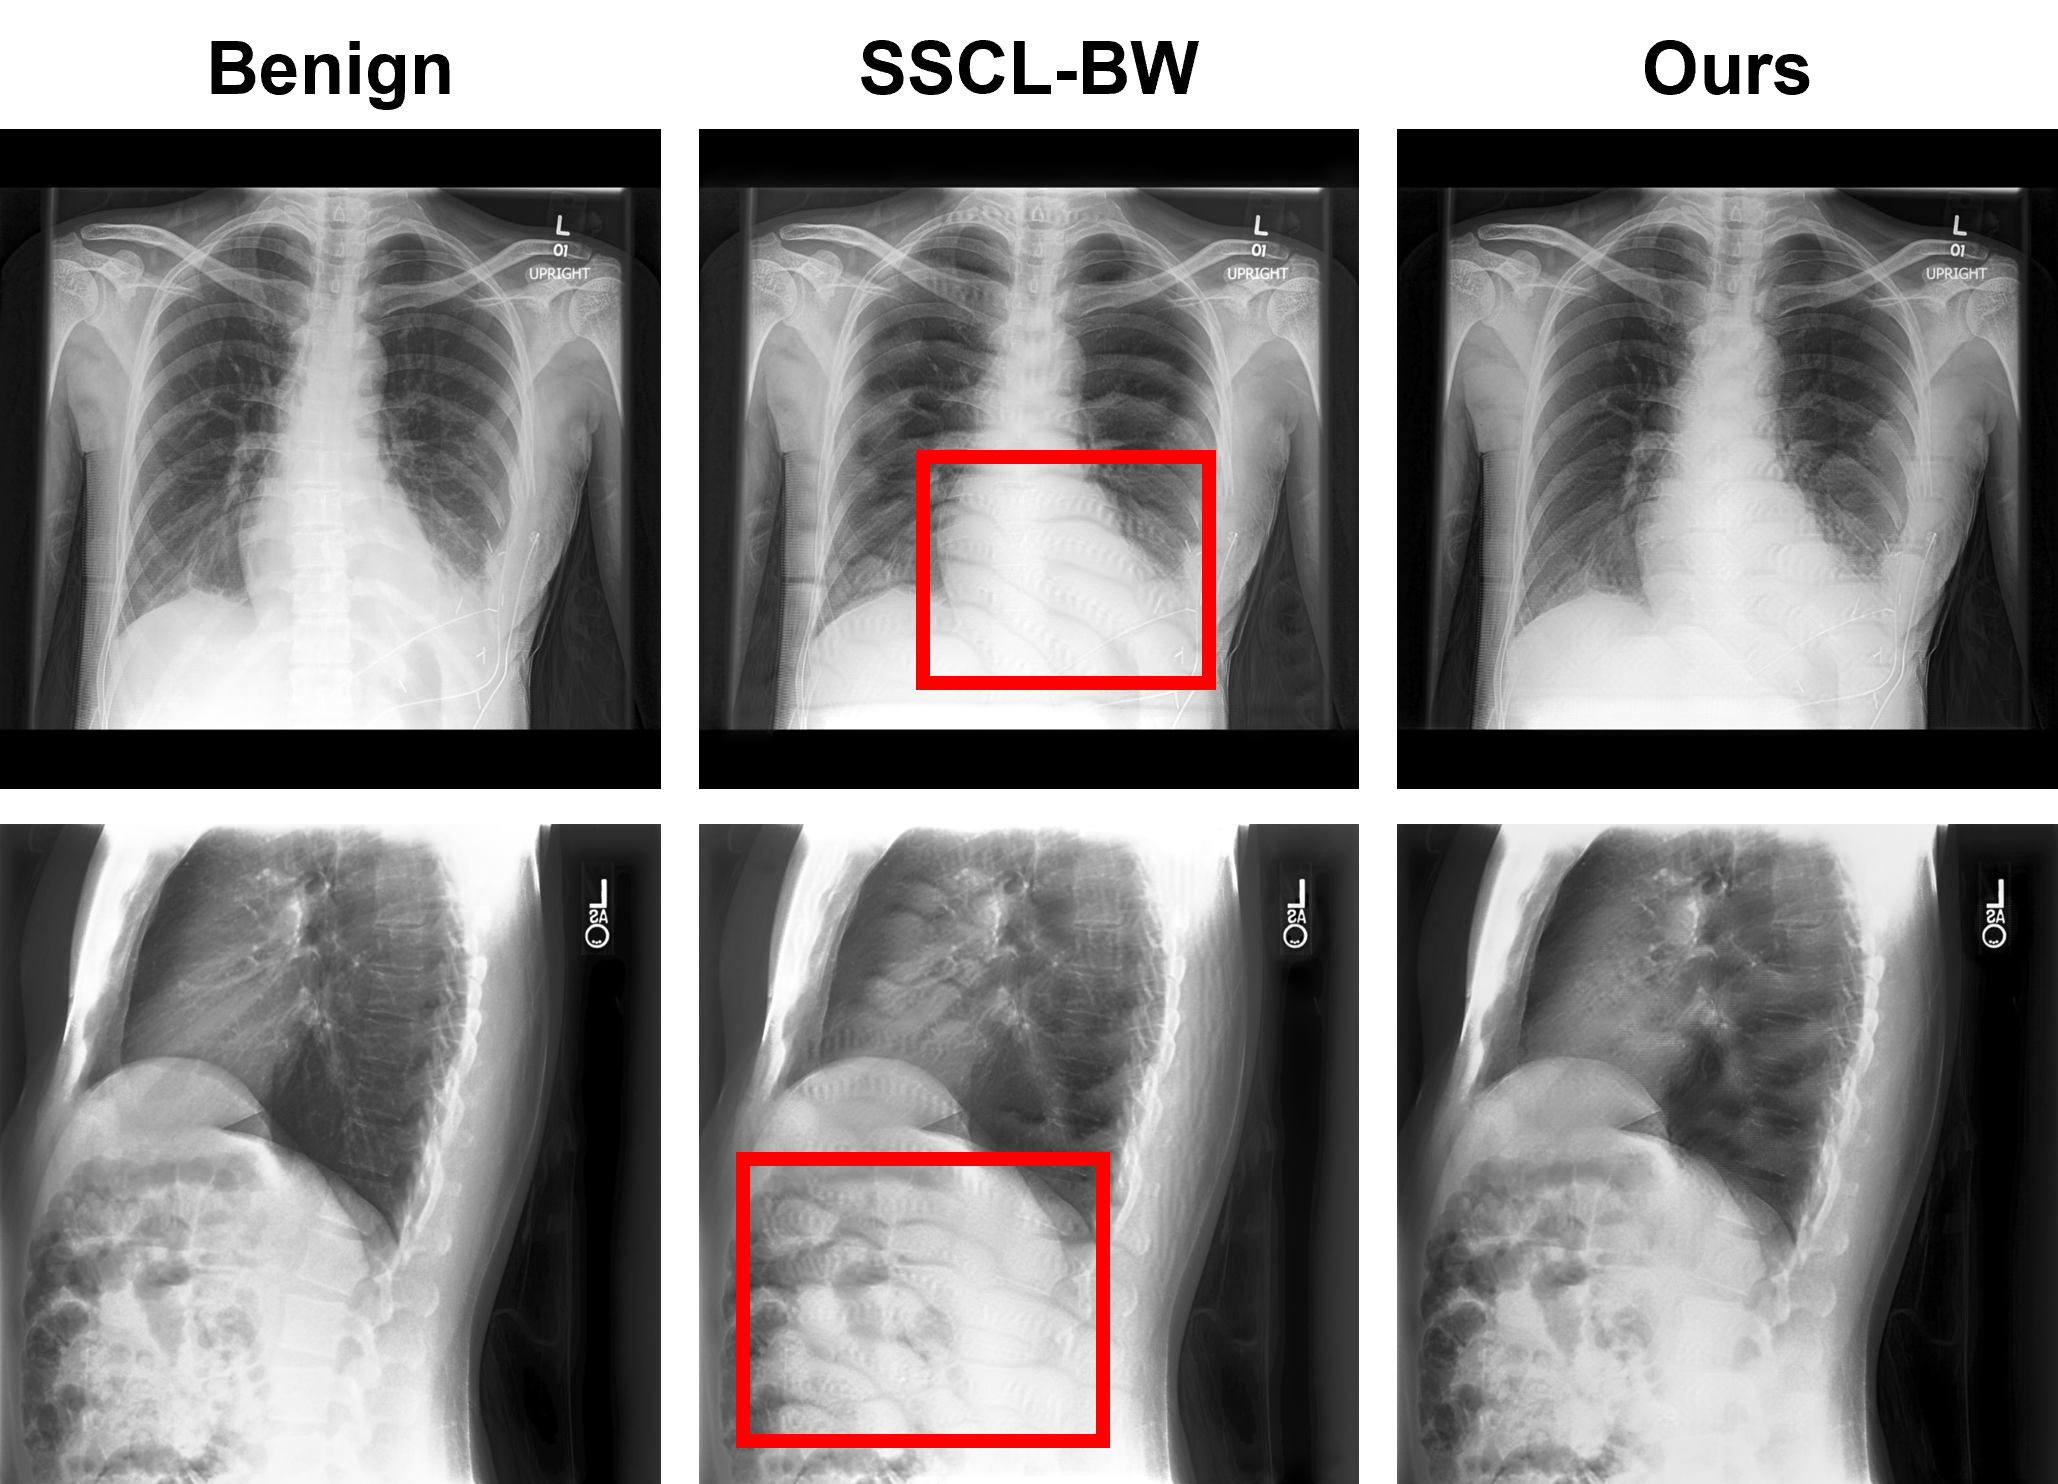

As shown in Table 1, our method demonstrates strong watermark effectiveness while maintaining imperceptibility, achieving highest BA of 84.88%84.88\% and WSR of 100%100\%. Among the poison-label baselines, BadNets and Blended attacks achieve high WSRs (100%100\% and 97.31%97.31\%). However, they rely on static trigger patterns that need to large enough to survive downsampling, making them easily detectable. WaNet watermarks fail to survive downsampling, only achieving a WSR of 16.81%16.81\%. Similarly, UBW-P with a WSR of 22.45%22.45\% scales poorly to the multi-label setting due to its untargeted nature. In the clean-label setting, Label-Consistent and SSCL-BW both reach WSR of 100%100\%. Label-Consistent relies on static triggers, while SSCL-BW generates strong perturbations (LPIPS of 0.023) that produce unrealistic anatomy, as shown in Figure 2. Results indicate that CXR datasets are well-suited for dataset watermarking, likely due to their limited visual diversity compared to natural images, allowing perturbations to remain in-distribution and exploit shortcut learning Jabbour et al. (2020).

Refer to caption

Figure 2: Example watermarked samples from SSCL-BW and X-Mark. Red box indicates region of strong perturbations, resulting in anatomically improbable structures that are easy to detect upon manual inspection. Saliency conditioning limits perturbations within salient regions (chest) while Laplacian regularization mitigates strong, unrealistic perturbations.